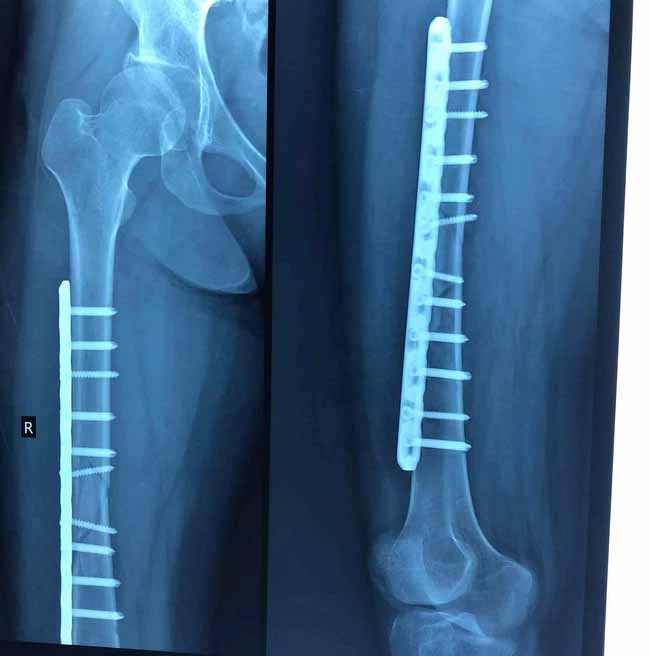

Cụ thể kết luận giám định sức khỏe của chị H: Sẹo vết mổ mặt ngoài đùi phải 03%. Gẫy 1/3 xương đùi phải còn phương tiện kết hợp xương 21%. Hiện chưa đánh giá được hết mức độ di chứng và biến chứng của tổn thương. Đề nghị giám định bổ sung sau nếu có căn cứ. Cơ chế hình thành thương tích do vật tày gây nên.

Kết luận tỷ lệ tổn hại sức khỏe 23% tính theo phương pháp cộng lùi.

Hình chụp chân của nạn nhân bị gãy

Về phía chị H., phản ánh với chúng tôi, chị cho biết bản thân là người khuyết tật (chân bị teo nhỏ, mất khả năng đi lại), do bị đau nhức nên đã nhiều lần nhờ anh T. tới trị liệu với giá 100 nghìn đồng mỗi lần. Sau khi sự cố xảy ra, chị H. phải nhập viện cấp cứu và thực hiện phẫu thuật. Chị H. cho biết, đến hiện tại sức khỏe của chị vẫn bị ảnh hưởng, chỗ bị gãy xương thường xuyên đau nhức khiến chị không tự chủ được một số sinh hoạt cá nhân.